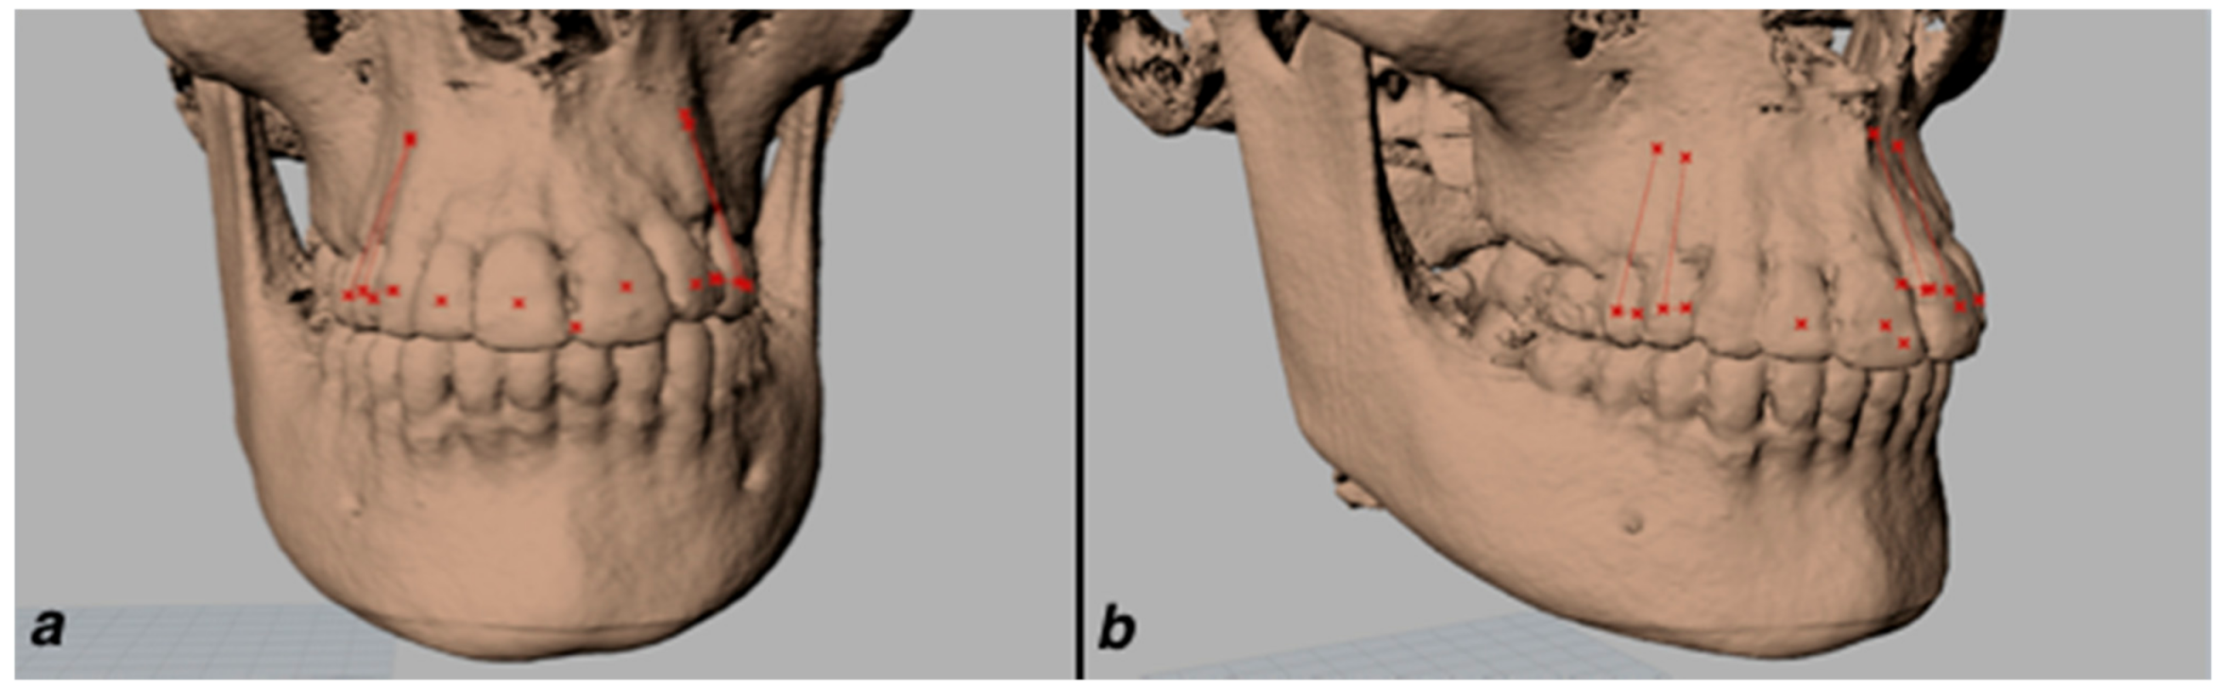

The landmarks were exported as Initial Graphics Exchange Specification IGES format to Rhinoceros Software (Robert McNeel and Associates, 3670 Woodland Park Avenue N., Seattle, WA 98103, USA) and buccolingual inclination and mesiodistal angulation were measured with the Grasshopper® plugin. Grasshopper was chosen because it is a visual programming language that allows for the creation of a digital workflow free from preconstituted software schemes. For each tooth, a proper vertical axis starting from Apex to Facial Axis Clinical Crown (FACC) and a proper horizontal axis starting from FACC to Occlusal were defined (Figure 2).

Figure 2.

Proper vertical axis and Proper horizontal axis of upper premolars on CBCT. The Proper vertical axis was defined from Apex to Facial Axis Clinical Crown (FACC) and the Proper horizontal axis from FACC to Occlusal Frontal (a) and lateral (b) view.

Moreover, a FACC plane was built by interpolation of single FACCs of each tooth. Buccolingual inclination was intended to be the angle between the Proper vertical axis and the projection of Proper horizontal axis on FACC plane (Figure 3).